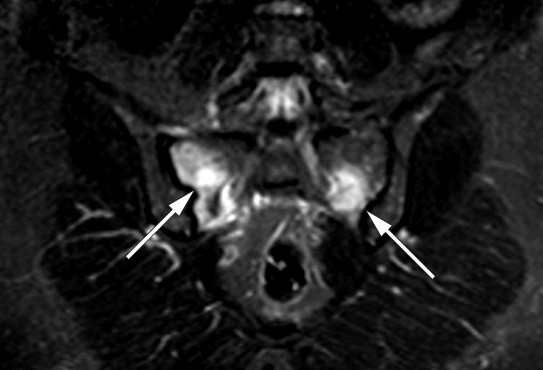

Behandlingen består i å seponere tilskudd av jernsakkarider, eventuelt gi tilskudd av peroral fosfat og vitamin D (2). Heldigvis ser det ut til at nyretubulidysfunksjonen og osteomalasien er reversible, men alvorlige beindeformasjoner kan være permanente. Ved kontroll fem måneder etter seponering av alle jerntilskudd, var pasienten i bedring. MR viste regress av patologiske forandringer (bildet til høyre). Pasienten trenger imidlertid fremdeles behandling for jernmangelanemien og får nå en annen type intravenøst jerntilskudd. Transfusjonsbehovet varierer, avhengig av hvor ofte hun får jern.